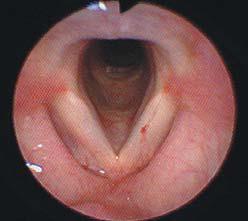

ENF-GP不仅提供了大而明亮的高分辨率图像,它基于ENF-P4的广受好评的光学元件,而且还由于其改进的光分布系统而具有增强的照明

ENF-GP不仅提供了大而明亮的高分辨率图像,它基于ENF-P4的光学元件,而且还由于其改进的光分布系统而具有增强的照明。

密切观察 远处观察

ENF-GP具有宽85°的视野,这允许声带的高清可视化。300毫米的长度使鼻腔和咽部的观察更容易,你将能够在观察喉部时在更舒适的距离从病人工作。